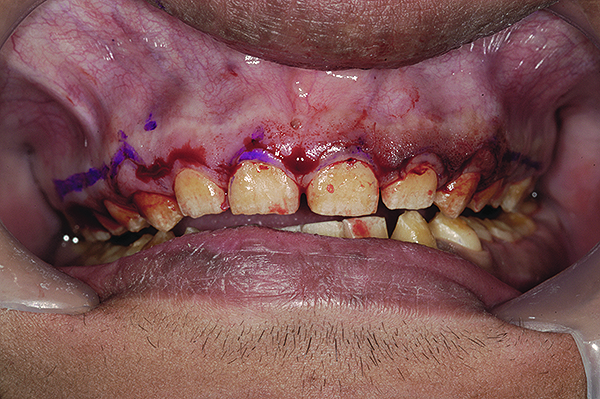

Figure 9. Marking gingival levels during crown lengthening.

Figure 9

Figure 10. Sutures placed with gingival levels corrected.

Figure 10

Esthetic Repositioning of Gingival Tissues

After administering local anesthesia, a periodontal probe was used to sound the bone on facial and interproximal aspects of all upper teeth. With the upper cuspids and bicuspids, there was insufficient distance between the proposed free gingival margin and the crestal bone (< 3 mm) (Figure 9). In such circumstances, merely trimming the gingival tissues without altering the bone could lead to a violation of biologic width, with its associated complications, one of which is the rebound of gingiva to its original level. Thus, for these teeth, an osteoplasty, along with gingival resection, was carried out. On most other teeth, including the lower anterior and posterior teeth, a gingivectomy was sufficient to achieve correction of gingival levels and proper width-to-length ratios of teeth.

An aspect of crown lengthening in cases of AI is to leave the gingival margins at the cementoenamel junction (CEJ) of the teeth. This is done so that any defective and pitted enamel is exposed and tended to in the final restorative design. Failure to do this may lead to recurrent gingival ill-health due to plaque accumulation in the pitted surfaces. In this case, however, upon raising the mucoperiosteal flap, it was found that the CEJ was missing as a result of total absence of enamel. Thus, the gingival margins were placed at the desired esthetic levels and sutured with monofilament sutures (Figure 10) and reevaluated after a healing period of 4 weeks (Figure 11).